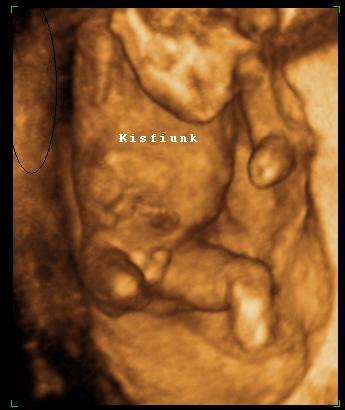

Szoval tudjátok mit nem értek??? Nem az a normál állapot, ha nincs a feje hátrahajtva? Mikor pl. magasságot mérnek, akkor sem érvényes, ha hátrahajtom a fejemet,nem? Sőt ha a fejemet hátrahajtom, az én nyakam is vastagabb lesz, és megrövidül nem? Szerintetek másnak a nyaki redőjét is úgy mérik, hogy megvárják, míg hátrahajtja a fejét?!?!? Nem értem az egészet, komolyan... mindegy, a lényeg, hogy még így is kevesebbet mértek. szoval holnap megyek 11:30-ra a Bolgárkerékre a 4d uh-ra és a kombinált tesztre utána.